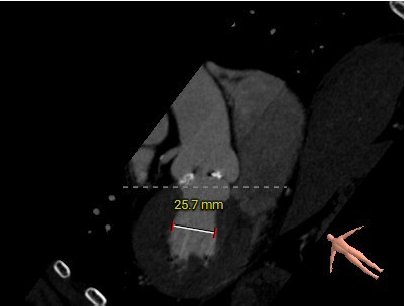

患者为71岁高龄男性,患者因反复胸闷15年,再发2月,5月慕名自行前来我院就诊。主动脉瓣听诊可闻及粗糙、高音调的喷射性收缩期杂音,余无特殊。术前超声显示瓣环直径28mm,左房37mm,左室收缩末内径55mm,左室流出道24mm。窦管高度17mm,内径39mm。瓣上最大流速3.7m/s,峰值压差56mmHg,平均压差34mmHg。诊断为主动脉瓣重度狭窄伴轻度关闭不全,二尖瓣轻中度反流。

主动脉根部评估:

左冠高度12.5mm右冠高度18.4mm,右冠脉开口高度大于瓣叶长度,SOV瓦式窦:平均周长径39.0mm,术中仍球囊预扩须密切注意冠脉灌注,STJ周长径39.2mm。

瓣叶重度钙化伴增厚,钙化分布不均匀,HU750积分1048mm²。